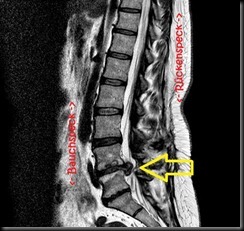

…für’s neue Jahr … na ja, eigentlich wollte ich Krankenhäuser nur noch von außen betrachten bzw. als Besucher betreten. Da wird aber mal wieder nix draus. Ich hab tüchtig Rücken und auf dem Bild erkennt man auch, warum. Der Pfeil zeigt, wo mir die Bandscheibe ordentlich auf den Nerv geht.

Und das mit ganz viel Aua! An der gleichen Stelle hatte ich vor einem guten Jahr schon mal einen Bandscheibenvorfall und die OP ist

Als ich die Diagnose bekommen habe, war ich allerdings etwas froh. Das hört sich vielleicht total bescheuert an, aber die Bilder vom MRT (Kernspin) bestätigen ja nun, dass ich kein Simulant bin. Ich hab’s oft zu spüren bekommen …bei Behörden, Amtsärzten bzw. Gutachtern, manchmal leider auch im näheren Umkreis … Und wenn man nicht mehr so funktioniert wie einst, ziehen sich so manche Leute zurück. Auch das tat und tut weh. Jetzt drück ich meinem Neurochirurgen die Daumen und hoffe, dass ihm der Nerv nicht wieder in die Quere kommt .